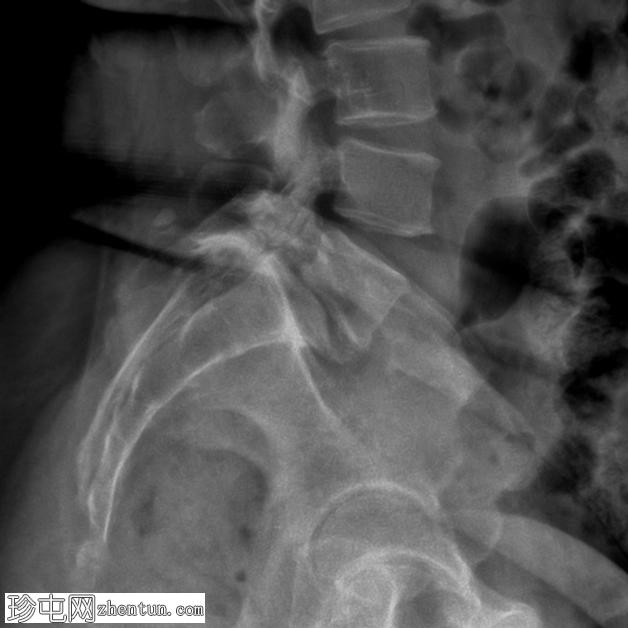

侧面

3.png

(放大)

L5-S1 椎体II度滑脱。

双侧椎间盘缺损。

L5-S1椎间盘间隙缺失,伴有退行性病变。